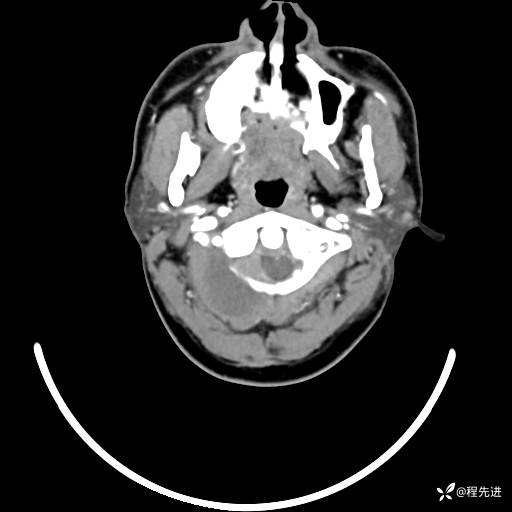

CT平扫+增强: